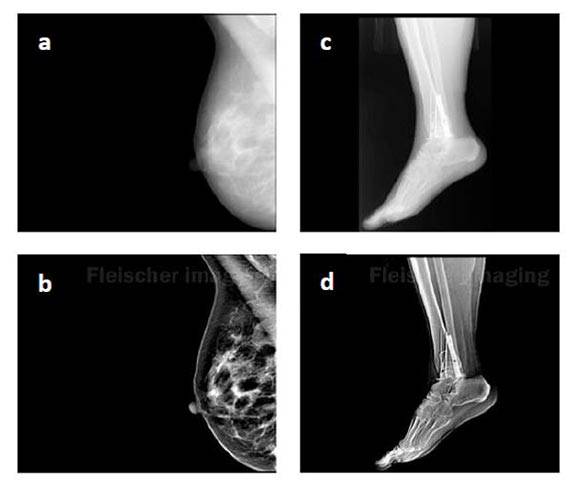

One of the six new technologies supported this year through the University's Intellectual Property Accelerator Fund is one that enhances X-ray images. The image above shows a comparison of a standard X-ray image (top row) and the computationally enhanced version (bottom row). (a,b) Mammogram of potentially cancerous breast. (c,d) Post-surgical image of ankle reconstruction. (Image courtesy of Jen-Tang Lu, Department of Electrical Engineering)

X-ray enhancement brings out details

Since their discovery in 1895, X-rays have become an essential tool for diagnosing broken bones, cancer and internal injuries. But X-ray images can be fuzzy and indistinct, which can lead to misdiagnosis and, in turn, unnecessary biopsies and treatments.

Jason Fleischer, associate professor of electrical engineering, and graduate student Jen-Tang Lu are enhancing these images using a technique that relies purely on post-image processing, so it does not require changes to the X-ray machinery or to technicians' techniques. Instead, the technology provides automated image enhancements based on models of physiology, machine learning and the use of a proprietary database of information that is specific to the part of the body and the type of image. The database draws on information provided by physicians and radiologists.

With support from the IP Accelerator Fund, the Fleischer team aims to transfer this technology to clinically relevant settings. While the approach can be used on any type of X-ray, the team is focusing on medical issues, such as tumor identification in ovarian cancer, improved mammogram CAT scans with reduced X-ray dosage, and enhanced imaging of fractures and bone healing.